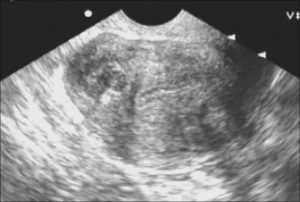

- При помощи ультразвукового исследования области малого таза и брюшной полости можно выявить возможные опухолевые процессы. При необходимости проводят трансвагинальную диагностику. Нужно это для того, чтобы рассмотреть место локализации фиброидного узла.

- УЗИ полости матки позволяет с точностью определить разновидность фибромы, количество узлов, размеры. Такой метод определяет и другие патологии эндометрия.

- Обнаружив уплотнение ткани, гинеколог отправляет пациента провести УЗИ малого таза. Ультразвуковое исследование позволяет врачу увидеть внутренние структуры репродуктивных органов женщины. УЗИ обнаруживает узлы. Иногда требуется проведение трансвагинального УЗИ, при котором ультразвуковой датчик вводится во влагалище, он предоставляет более четкие снимки, поскольку находится ближе к матке.

- Ультразвуковое исследование органов малого таза трансвагинальным датчиком. Метод позволяет визуализировать патологические участки, так как они отличаются по эхогенности. Патологический участок нередко выглядит как узел. Эта патология носит название фиброзной миомы. По результатам исследования также возможно диагностировать увеличенную в размерах матку.